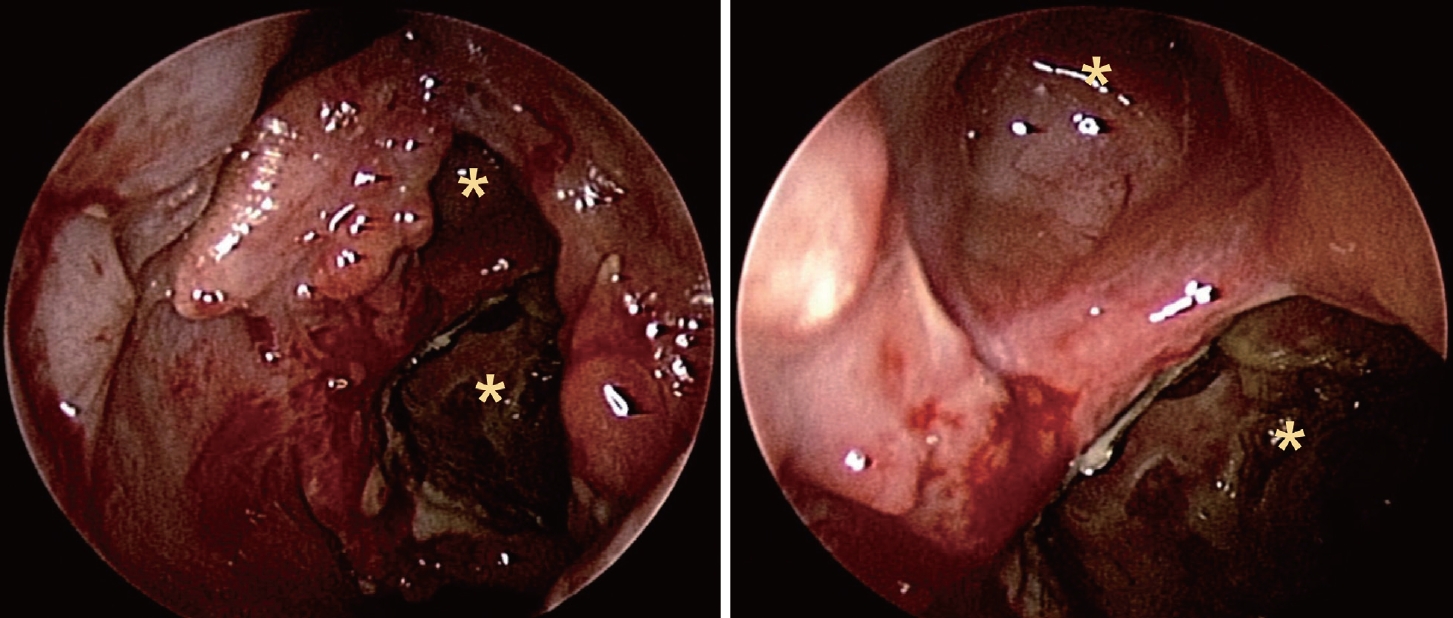

증 례이전 안면 외상, 수술력 포함하여 특이병력 없이 건강하였던 41세 여자 환자가 15년 전부터 서서히 악화되는 좌측 안와 주위통, 안구돌출을 주소로 내원하였다. 어지럼증, 사지 위약감, 실조 등의 신경학적 증상은 부인하였고 이외 다른 비증상, 안증상도 부인하였다. 비내시경 검진상 우측 비중격 만곡증 및 좌측 비강의 중비도에 정상점막으로 덮힌 팽창성 돌출 병변이 관찰되었다(Fig. 1).

이에 점액낭종을 동반한 좌측 사골동 섬유 이형성증으로 진단하였고, 임상증상이 병변의 위치와 상관 관계가 일치하고 점액낭종이 동반되어 있기에 부비동 내시경을 이용한 수술을 계획하여 시행하였다. 전신마취하 내시경 검진 후 좌측 섬유이형성증 감량술, 점액낭종 조대술 및 좌측 중비도 상악동개방술(middle meatal antrostomy)을 시행하였다. 특징적인 소견으로 프리어 엘리베이터(freer elevator), 절단 겸자(cutting forceps)로 병변의 전방 격막을 제거하자 한차례 점액낭종이 조대되었고 이어 미세절삭기(debrider)로 후상방에 위치한 두 번째 점액낭종의 조대술을 시행하였다. 그 내부에는 갈색의 점액성 분비물이 가득 차 있었다(Fig. 3).

NotesAuthor Contribution Conceptualization: Seung Heon Kang, Hyun Jik Kim. Data curation: Seung Heon Kang, Hyunkyung Cha, Seung Cheol Han. Formal analysis: Seung Heon Kang, Hyun Jik Kim. Funding acquisition: Seung Heon Kang. Investigation: Seung Heon Kang. Methodology: Seung Heon Kang. Project administration: Seung Heon Kang. Resources: Seung Heon Kang. Supervision: Hyun Jik Kim. Validation: Seung Heon Kang. Visualization: Seung Heon Kang. Writing—original draft: Seung Heon Kang. Writing—review & editing: Seung Heon Kang. Fig. 1.Endoscopic finding of expansile extruding mass covered with normal mucosa in left middle meatus. Fig. 2.Left ethmoid fibrous dysplasia combined with mucocele (A) eroded lamina papyracea (B) involvement of pterygoid plates (C) hypoplastic left maxillary sinus and right septal deviation. Fig. 3.Endoscopic findings of operation (A) brownish content spilled out from the mucocele (B) visualization of septated mucoceles (asterisks) after removal of anterior wall of fibrous dysplasia (C) after marsupialization. Fig. 4.Histopathologic findings of FD, pathologic report of FD: osteoid trabeculae that are narrow, curvilinear or irregularly-shaped are arranged haphazardly in a background of dense fibroblastic stroma (hematoxylin and eosin, original magnification ×20). FD: fibrous dysplasia. REFERENCES1. Weinstein LS, Shenker A, Gejman PV, Merino MJ, Friedman E, Spiegel AM. Activating mutations of the stimulatory G protein in the McCune-Albright syndrome. N Engl J Med 1991;325(24):1688-95.